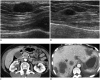

Breast metastases from extramammary malignancies are uncommon. The most common sources are lymphomas/leukemias and melanomas. Some of the less common sources include carcinomas of the lung, ovary, and stomach, and infrequently, carcinoid tumors, hypernephromas, carcinomas of the liver, tonsil, pleura, pancreas, cervix, perineum, endometrium and bladder. Breast metastases from extramammary malignancies have both hematogenous and lymphatic routes. According to their routes, there are common radiological features of metastatic diseases of the breast, but the features are not specific for metastases. Typical ultrasound (US) features of hematogenous metastases include single or multiple, round to oval shaped, well-circumscribed hypoechoic masses without spiculations, calcifications, or architectural distortion; these masses are commonly located superficially in subcutaneous tissue or immediately adjacent to the breast parenchyma that is relatively rich in blood supply. Typical US features of lymphatic breast metastases include diffusely and heterogeneously increased echogenicities in subcutaneous fat and glandular tissue and a thick trabecular pattern with secondary skin thickening, lymphedema, and lymph node enlargement. However, lesions show variable US features in some cases, and differentiation of these lesions from primary breast cancer or from benign lesions is difficult. In this review, we demonstrate various US appearances of breast metastases from extramammary malignancies as typical and atypical features, based on the results of US and other imaging studies performed at our institution. Awareness of the typical and atypical imaging features of these lesions may be helpful to diagnose metastatic lesions of the breast.